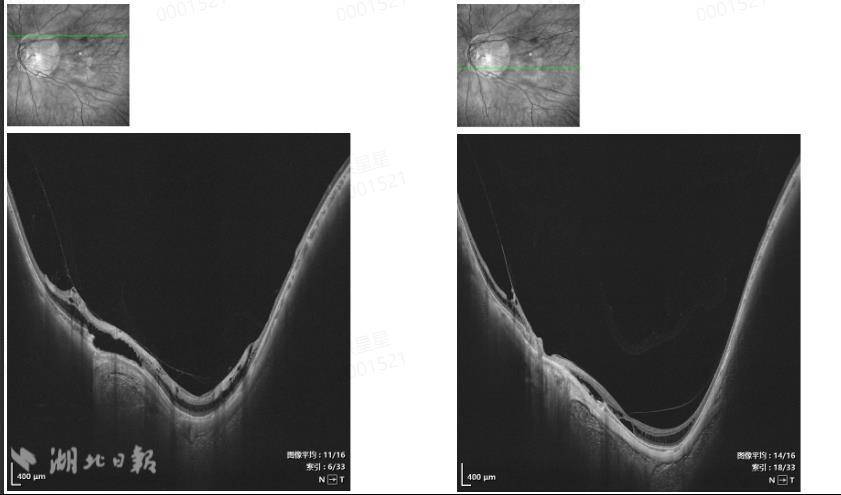

湖北日报讯(记者于金一、通讯员裴霓裳)武汉一男子近一年来视力不断下降,但一直不予理睬,直到被诊断出患有视网膜劈裂症。吴先生(化名),41岁,是一名极高度近视患者,双眼近视度数为2000度。这一年来,他不断感觉到自己的视力在慢慢下降。近期,他的左眼视力受到严重影响,甚至影响了他的正常工作和生活。他这才认真起来,来到湖北爱尔眼科医院特约门诊向邢一桥寻求治疗。经查,吴先生裸眼视力为0.02,戴眼镜矫正视力为0.5;左眼未改变的视力为0.02,但戴眼镜后的视力仅为0.1。 OCT检查扫描显示,其右侧黄斑神经上皮层存在低反光暗腔。眼睛,像桥梁一样相连;左眼黄斑区视网膜表面可见中高反射光带,延伸至大网膜。左眼神经上皮层内及下有低反射暗腔,有的像桥一样相连。进一步检查证实,吴先生因高度近视导致双眼视网膜劈裂。她的左眼情况较严重,需要手术治疗,而右眼因高度近视,周围有退行性病变,需要择期预防性激光治疗,以防止进一步发展为视网膜裂孔或视网膜脱离等严重并发症。患者眼睛检查的结果。 “什么是视网膜劈裂症?”得知检测结果后,吴先生充满了惊喜。 “这是高度近视常见的眼底并发症,眼轴过度拉长导致视网膜变薄,这反过来又引起视网膜神经上皮层的层间分离。治疗的主要原则是定期观察和控制病情进展,必要时进行医学干预,防止视力进一步受损。”邢一桥解释说,吴先生的左眼病情影响到黄斑,必须手术切除玻璃体和裂开区的内界膜,以恢复黄斑的正常形状,防止视力进一步下降。右眼需要择期激光治疗。上周,邢一桥成功进行了一次激光治疗。 11月28日,吴先生左眼接受后玻璃体切除术,病情稳定,逐渐康复。湖北爱尔眼科医院基金疾病专家邱娇提醒,视网膜劈裂早期可能没有明显症状,但部分患者可能会出现视力下降、视野缺损、闪光等症状。光。由于高度近视患者的视网膜本来就脆弱,精神分裂症会逐渐进展,甚至诱发视网膜脱离。他建议高度近视患者每3-6个月进行一次散瞳眼底检查,并利用OCT(光学相干断层扫描)准确诊断斜视和乳沟厚度;日常尽量避免蹦极、跳水、过山车、拳击等高速冲击运动;如果持续用眼超过40分钟,应休息5-10分钟,看书时保持30厘米以上的距离,尽量不要在黑暗的环境下使用电子设备。